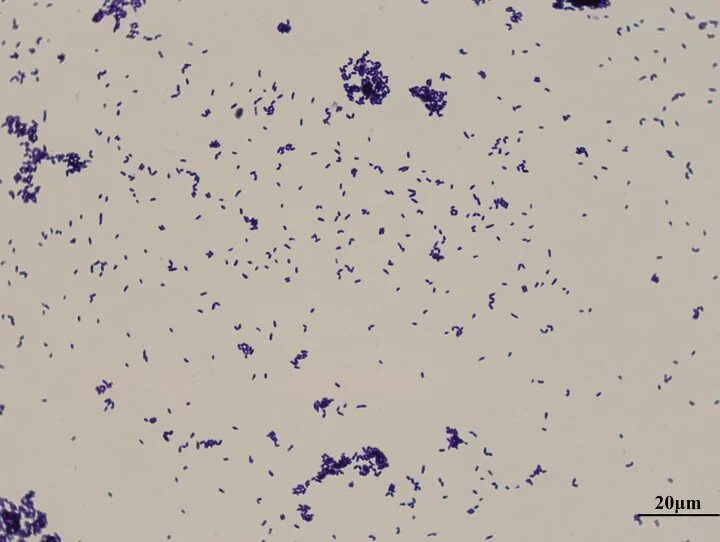

Corynebacterium spp в мазке у мужчин